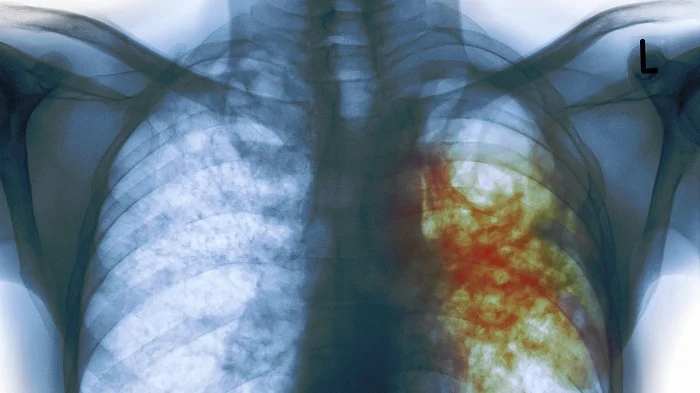

Umuyobozi w’agateganyo w’ishami ryo gukumira no kurinda idwara mu Kigo cy’Igihugu gishinzwe Ubuzima (RBC), Dr Patrick Migambi, avuga ko mu Rwanda hapfa umuntu umwe ku munsi, azize indwara y’igituntu.

Ati “Indwara y’igituntu yica abantu benshi kuko buri mwaka yica abarenga 1,100,000 ku Isi, ni ukuvuga abantu bapfa buri munota. Hano mu Rwnda, buri munsi igituntu gihitana umuntu.”

Avuga ko mu Rwanda, imibare yagiye igabanuka kuko abicwa n’igituntu bagabanutse ku kigero cya 69%.

Mu Rwanda ngo abagaragaweho indwara y’igituntu mu mwaka wa 2023-2024, 90% bafashe imiti neza kandi barakira.